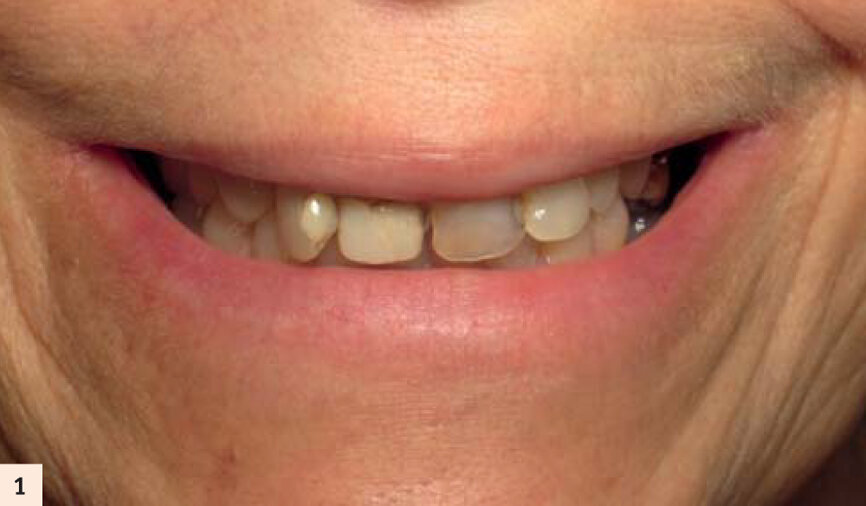

Nous allons voir à présent les différentes applications « Hi Tech » en implantologie au travers d’un cas, tant d’un point de vue clinique que pédagogique. Notre patiente a une cinquantaine d’années, elle est en bonne santé et non fumeuse.

Elle porte un appareil amovible au maxillaire, côtoyant 5 dents naturelles. Elle souhaite une solution fixe (Figs. 1, 2, 3). Après empreintes, mise en articulateur et confection d’un guide radiologique, un examen 3D est réalisé. L’analyse des fichiers DICOM’s transférés sur le logiciel de planification CoDiagnostiX, confirme un faible volume osseux.5Les sinus ont fortement pneumatisé le maxillaire et les parois antérieures sont au niveau des canines.

Sourire non gingival de la patiente.